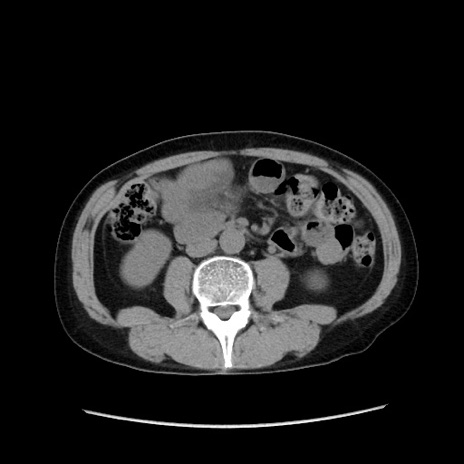

症例37(横断像)

【症例】40歳代 男性

【主訴】腹痛

【現病歴】4時間ほど前に電車に乗車中に臍部上より腹痛出現。徐々に増悪し起立困難となり、救急外来受診。生ものは数日食べていない。今朝お雑煮を食べた。

【身体所見】BT 36.8℃、BP 117/84mmHg、HR 91/min、SpO2 97%、苦悶様、腹部:臍上部広範囲圧痛あり、反跳痛±

【データ】WBC 8100、CRP 0.03